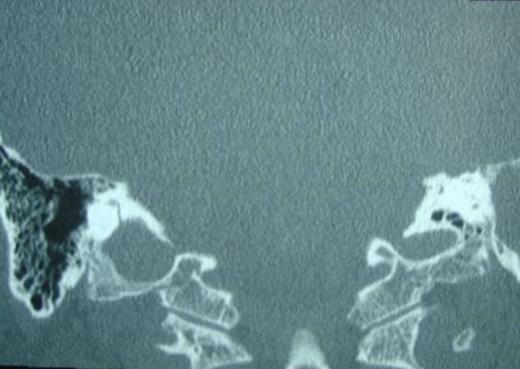

When surgery was attempted, cochleostomy revealed complete obliteration of the scala tympani. Efforts to insert the electrode through the scala vestibuli were also unsuccessful. The procedure was abandoned and a subsequent high resolution CT scan showed complete ossification of the left cochlea and but a patent cochlea on the right (Fig. 3 and 4). Twenty days following the initial attempt, a right cochlear implantation was successfully performed. Following mapping, programming, and aural rehabilitation, the patient was able to understand speech and use the telephone.